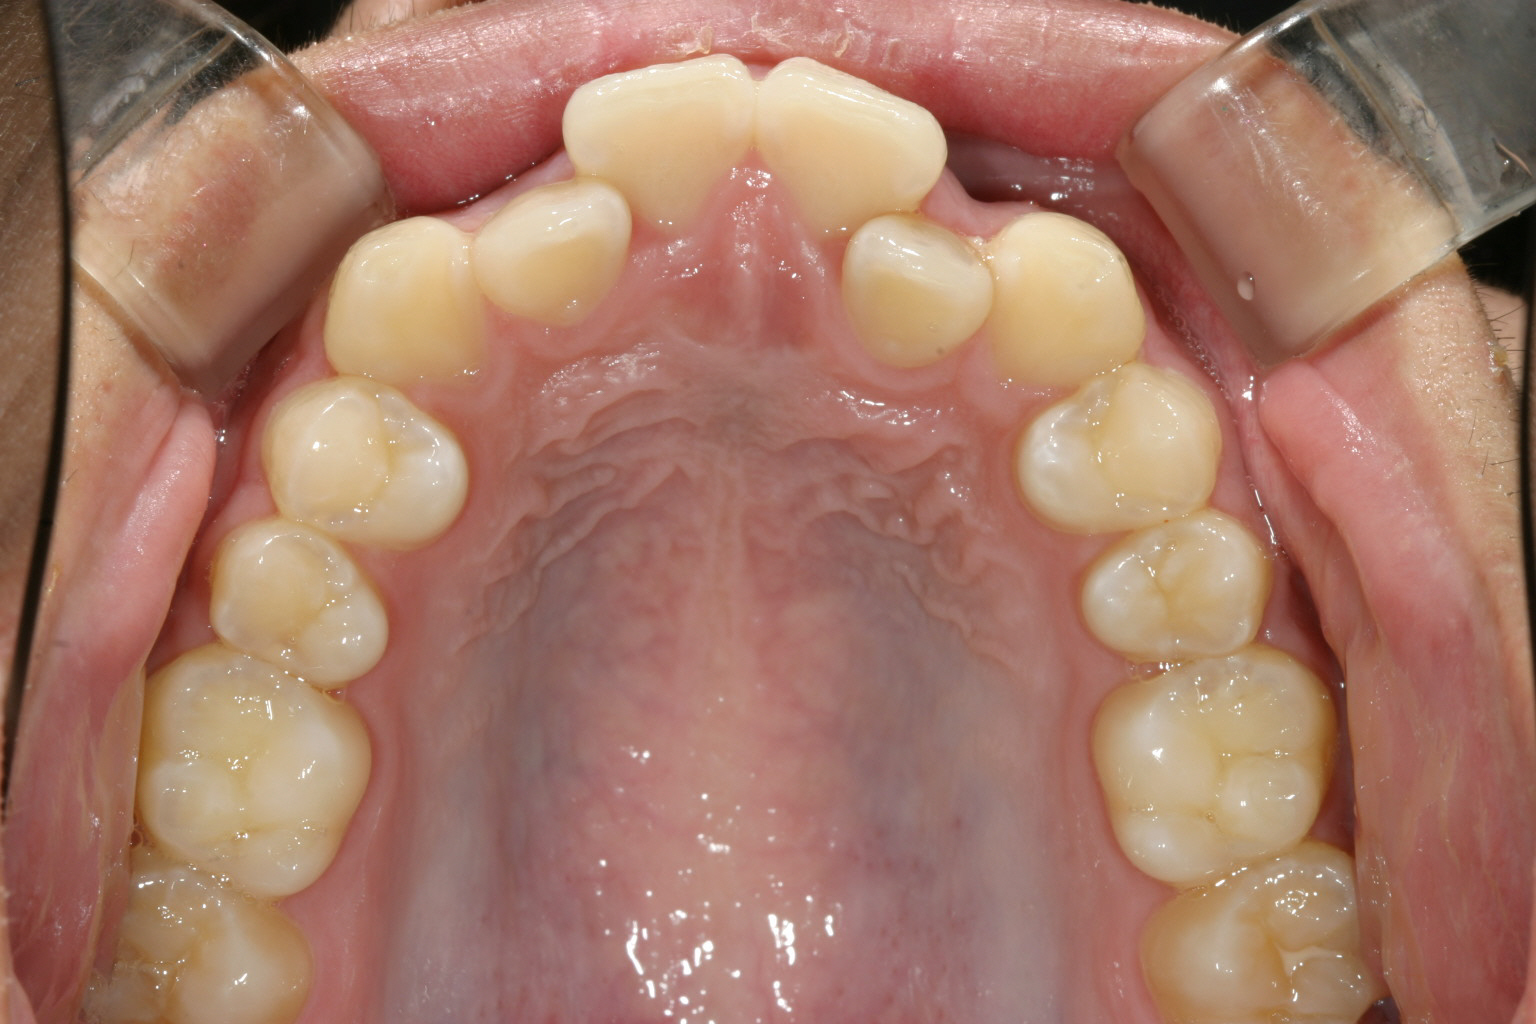

歯列弓が狭い為に前歯が並ばずガタガタしています。

アーチを広げ綺麗に配列しました。

当院ではよくあるケースで犬歯間が狭くなっている為上手く前歯が並んでいません。

と言う事で少しアーチを広げる事によりこの様に綺麗な咬み合わせに改善します。